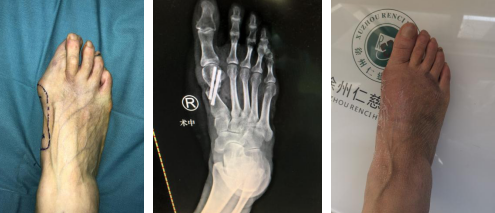

55岁女性,发现右足拇外翻畸形10年

术前(左图)术中 (中图)术后1个月(右图)